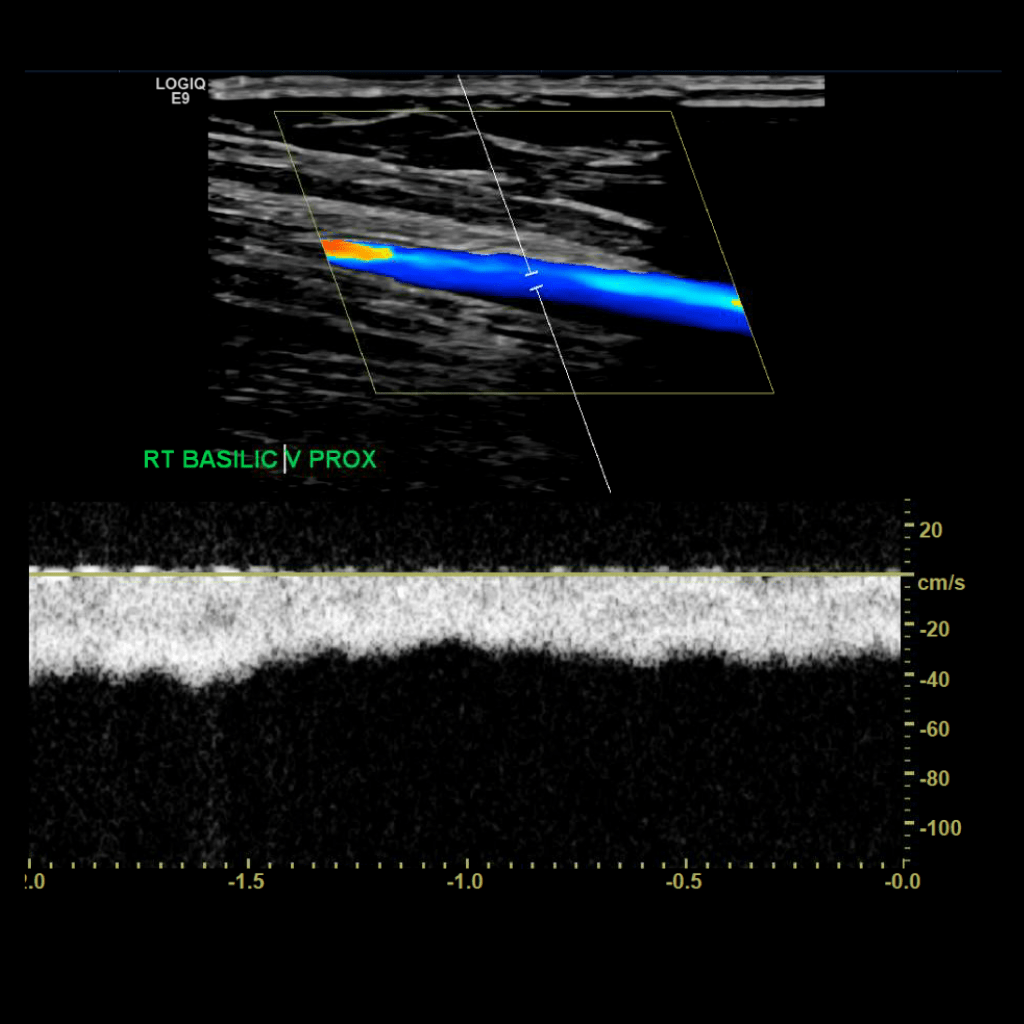

Scan the basilic vein in grey scale, compression, color doppler and spectral doppler

Thrombus of the right basilic vein